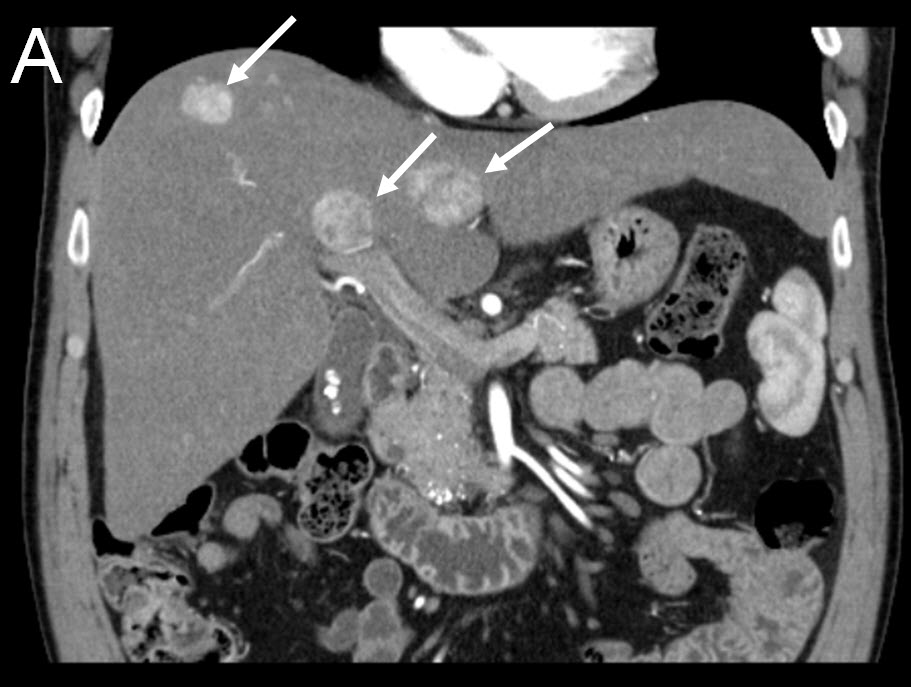

Treating Multiple Liver Tumors with Drug Eluting Beads (DEB TACE)

|

| (A) Coronal CT-scan of patient with multiple liver tumors |